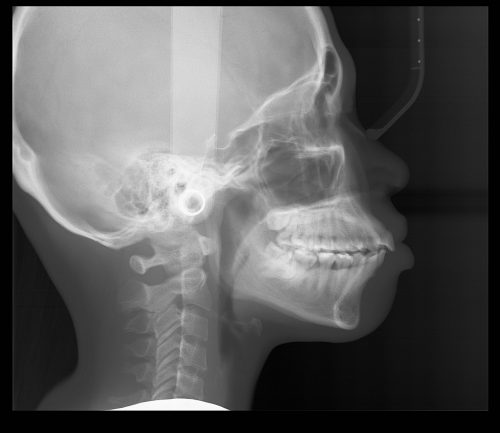

Skull Anatomy for Dental Cone Beam Users

Viewing Calcification of Carotid Arteries in a Panoramic Radiograph

Assessment of Obstructive Sleep Apnea Using a Dental Cone Beam